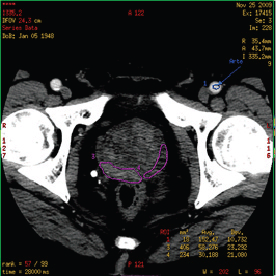

Figure 2. Region of interest (ROI) in prostate CT perfusion: the manually drawn ROI containing malignant tissue (purple contour on the right side of prostate gland) and healthy tissue (purple contour on the left side of prostate gland).

For quantitative analysis, a region of interest (ROI) was manually drawn along the visible margins of the obvious PCa by electronic cursor, in all the sections in which tumour was visible (area range: 48–221 mm2, mean value: 128 ± 46 mm2) and saved for each patient.

ROIs were chosen so that on all images they were drawn over regions of tumour throughout the image series irrespective of motion. If excessive motion artefacts precluded drawing a region of interest that stayed within the tumour margins in all the images of the CTp scan, the patient was excluded from the study (Figure 2).